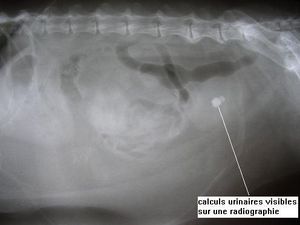

– La plupart des calculs urinaires (struvites, oxalate de calcium, phosphate de calcium) peuvent être mis en évidence sur une radiographie.

D’autres, non radioopaques vont nécessiter la réalisation soit d’une radiographie après injection d’un produit de contraste, soit d’un examen échographique.